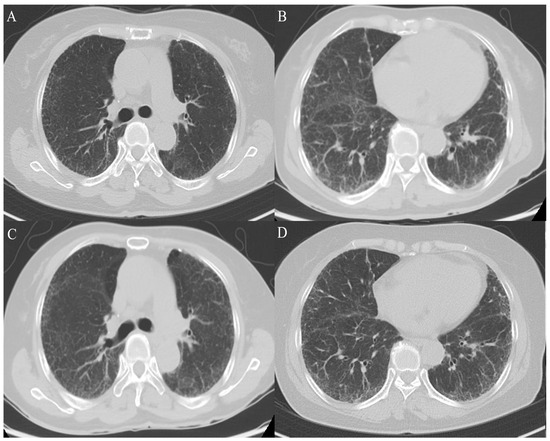

2. Case Presentation